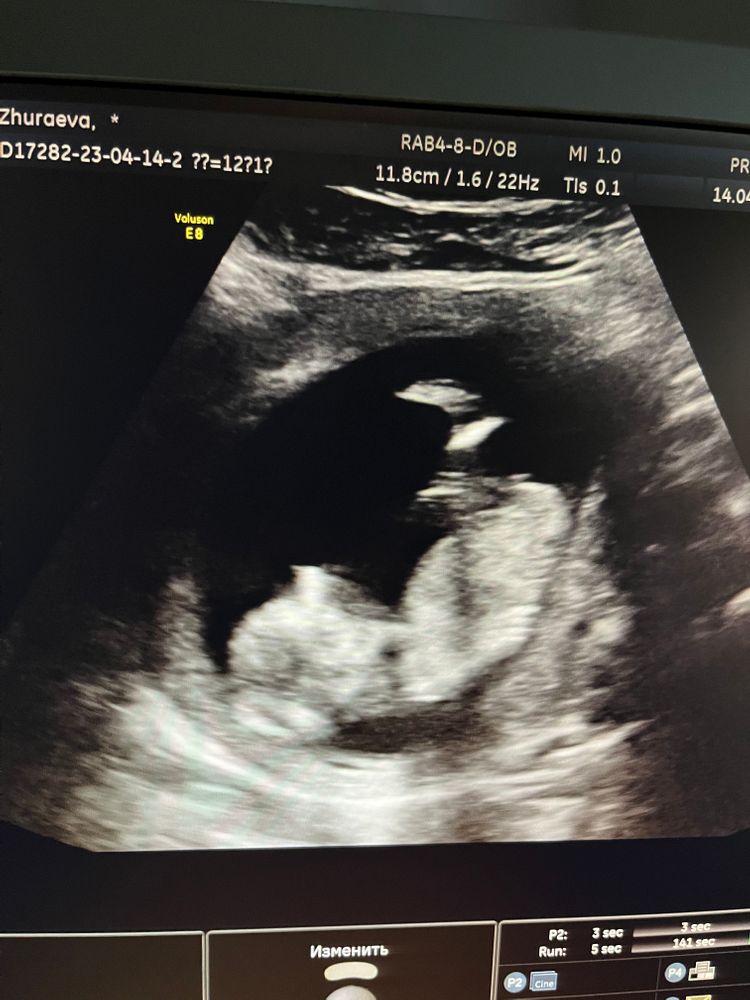

Были на 1 скрининге , врач сказала что видит уже на 80% кто там 🤰 так не терпится узнать. Может кто понимает по фото кто же там)))

На первом скрининге лучше не доверять прям, я конкретный пол не вижу , они ж там по бугорку определяют врачи , сходите на определение Пола в 16 недель

На последнем фото если это бугорок, то думаю мальчик . А на УЗИ не сказали кто?